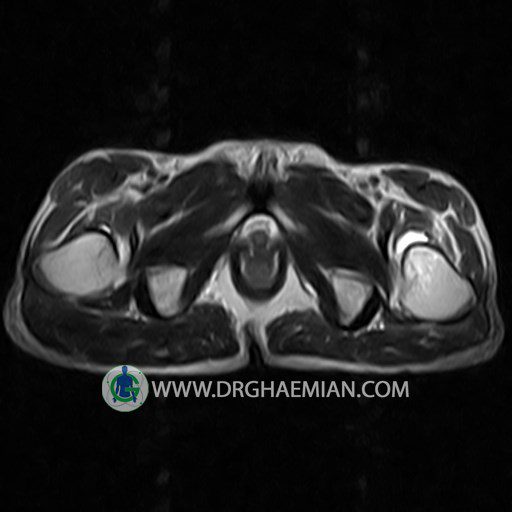

پزشکان اغلب از تصویربرداری ام آر آی برای تشخیص و درمان عارضه های پزشکی که فقط با استفاده از اشعه ایکس یا میدان مغناطیسی و امواج رادیویی قابل مشاهده است، استفاده می کنند. دستگاه ام آر آی تصاویر دقیق از ساختار های داخلی بدن ایجاد می کند. در این کیس استئومیلیت لگن، آتروز و سنیویت دیده می شود.

HIP JOINT MRI

( without contrast )

Technique : coronal STIR , coronal T2 , Axial T1 , axial T2 .

REPORT:

– Heterogeneous signal change (high T2/STIR , low T1) in proximal metaepiphysis of left femur without articular surface irregularity suggestive for bone bruise (stress fracture?), osteomyelitis & arthritis and marrow infiltration (less probable)

– Left hip joint effusion suggestive for synovitis

are seen.

COMMENT: Clinical correlation and MRI with contrast are recommended.